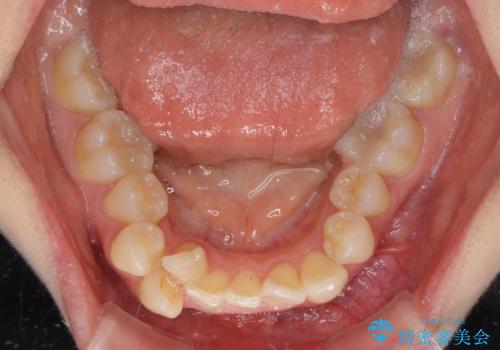

デコボコで磨きにくい歯列 ワイヤー装置での抜歯矯正で歯磨きをしやすく

- デコボコの歯列で歯磨きがしにくいことを気にして来院された患者様です。

右側の上下は歯が重なり合って、内側に移動してしまうほどであり、それに伴って正中の位置が右側にずれている状態でした。

上下左右の第一小臼歯4本を抜歯して行うことになりますが、それだけでは咬み合わせの改善や正中位置の改善が困難であると判断されたため、アンカースクリューを用いた補助装置を併用することで、スムーズかつより良い仕上がりを目指すこととしました。